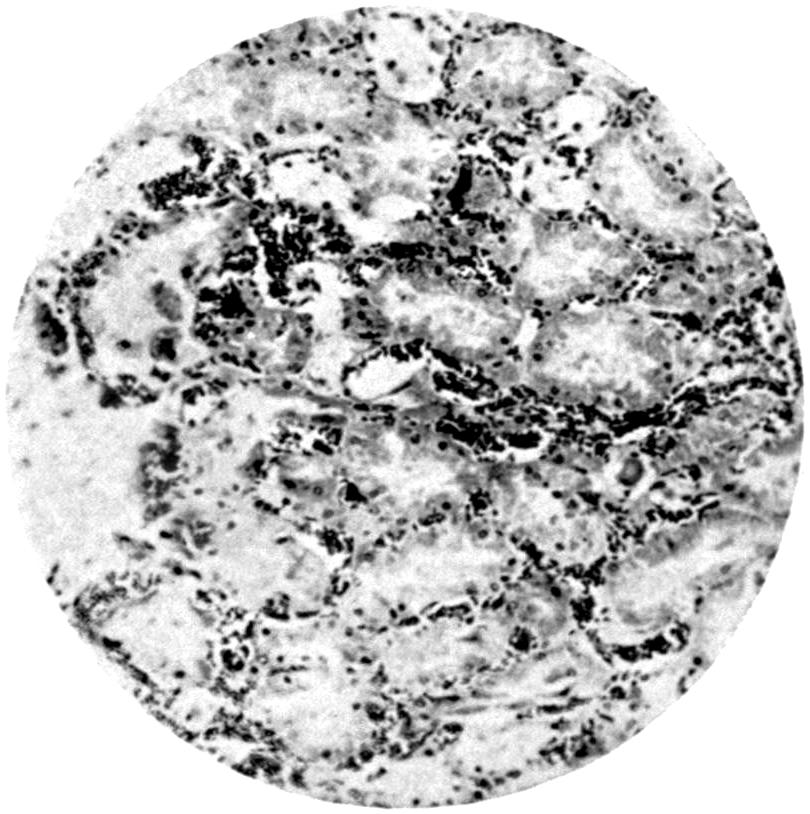

Plate I. 92